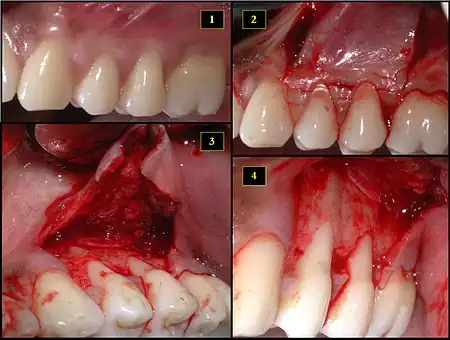

Subepithelial connective tissue graft

- Recipient site exhibits gingival recession on both premolars and first molar (molar recession is not an esthetic issue and will not be treated)

- Incisions prior to flap reflection

- Full thickness flap elevated

- Another viewpoint of the flapped recipient site